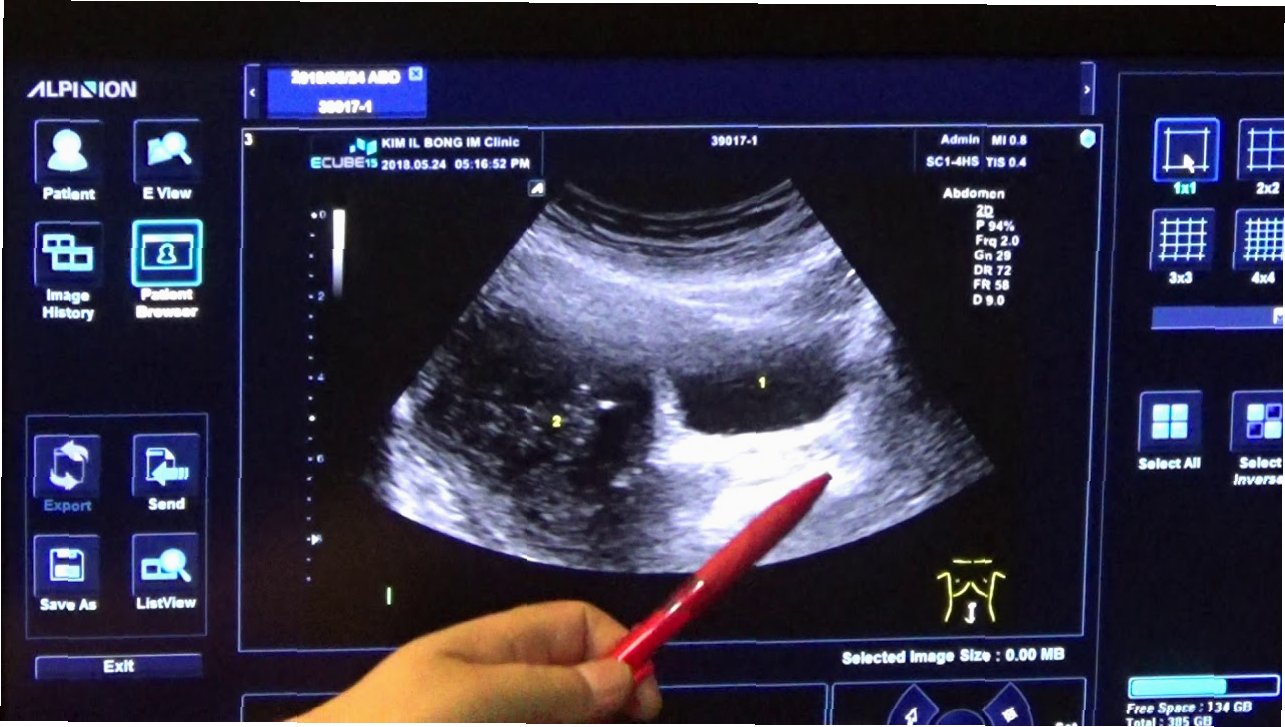

프랑스 출신의 유명 키즈모델 틸란 블롱도(24)가 최근 건강 문제로 투병 중이라는 소식이 전해졌습니다. 그는 6살 때 '세계에서 가장 아름다운 소녀'로 선정되며 세간의 주목을 받았고, 이후에도 여러 명품 브랜드의 광고 모델로 활동해왔습니다. 하지만 최근 SNS를 통해 자신이 난소 낭종으로 수술을 받았음을 알렸습니다. 블롱도는 '배가 너무 아파서 응급실에 실려 갔다'며, 자궁에 5~6cm 크기의 난소 낭종이 발견됐다고 밝혔습니다. 그는 수술 후 회복 중이며, 의료진과 가족에게 감사의 마음을 전했습니다.

난소 낭종은 난소에 물이 찬 혹이 생기는 증상으로, 난소는 여성의 배란과 호르몬 생성을 담당하는 중요한 기관입니다. 일반적으로 두 가지 종류의 난소 낭종이 있으며, 기능성 낭종은 난포가 제대로 성숙하지 못해 생기는 것이고, 난포성 낭종은 배란 후에도 난포가 남아 있을 때 발생합니다. 대부분의 경우 크기가 크지 않으면 자각 증상이 없지만, 일부는 복부 팽만감이나 통증을 유발할 수 있습니다.